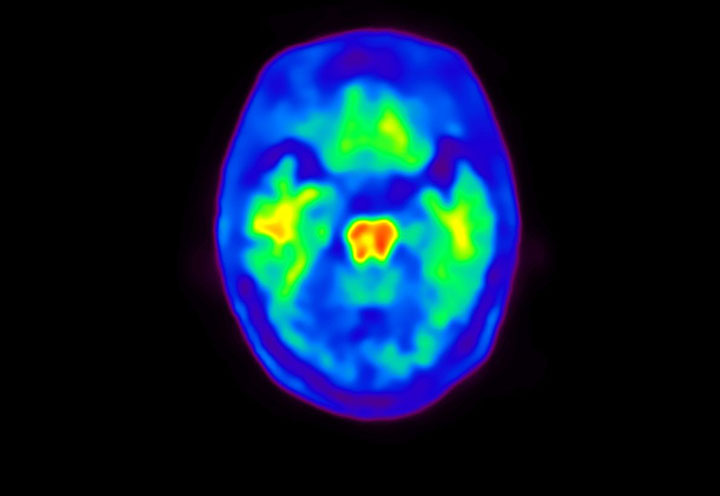

Head / Case4 : Amyloid

Sagittal

Courtesy : Kindai University Hospital

- Imaging protocol

- Injected dose: 3.21 MBq/kg, 18F-Flutemetamol

- Uptake time: 100 minutes

- Scan time: 20 minutes